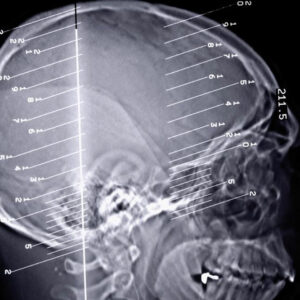

An overview of the types of epilepsy seizures

The human body can perform all its functions seamlessly when every organ of the body works in unison to perform the task. A slight change in the functions of the organ can disrupt the entire functioning of the body. Epilepsy seizures are a kind of disorder that occurs when we there is a problem in our brain’s electrical system.